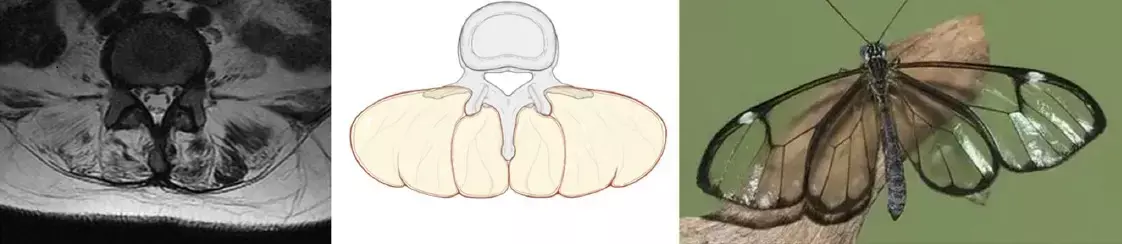

Muscle atrophy and fat infiltration result in extensive fat deposits in the posterior paraspinal muscles, which, when viewed on T2 axial MRI along with the vertebral body and spinous processes, produces a distinctive imaging appearance similar to that of a glassy-winged butterfly (Greta oto), which can be referred to as the “Greta oto” sign.

There were three females and one male, aged from 38 to 55 years. MRI examinations showed significant atrophy and fat infiltration of the bilateral erector spinae muscles, as well as varying degrees of atrophy observed in the multifidus muscles. The fatty degeneration in the erector spinae and multifidus muscles, together with the vertebral bodies and spinous processes, produced a distinctive imaging manifestation resembling a “Greta oto” sign on axial T2-weighted MRI scans in all patients. Ultimately, all four patients were referred to the neurology department, where the diagnosis of myopathy was confirmed by muscle biopsy (one myopathy with early-onset Paget disease and frontotemporal dementia type 1 (IBMPFD), one HMGCR antibody-positive myopathy, one myotonic dystrophy and one limb-girdle muscular dystrophy.

The authors concluded – “The Greta Otto sign may be a specific MRI manifestation of axial myopathy with low back pain as the primary clinical manifestation. This sign may help clinicians identify axial myopathy and reduce the likelihood of misdiagnosis as nonspecific low back pain.”